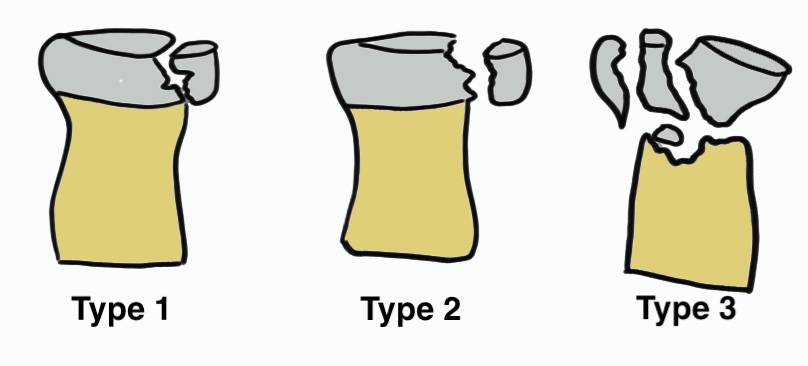

Mason Classification

| Type 1 | Type II | Type III |

|---|---|---|

|

Minimally displaced fracture < 2 mm No block to rotation |

Displaced fracture radial head > 2 mm Reconstructable |

Comminuted fracture radial head Unreconstructable |

| Non operative |

ORIF + LCL repair / reconstruction +/- MCL repair / reconstruction if unstable |

Radial head replacement + LCL repair / reconstruction +/- MCL repair / reconstruction if unstable

|

Regan and Morrey classification of transverse coronoid fractures

Elbow stability related to size of coronoid fragment

| Type I | Type II | Type III |

|---|---|---|

| Small coronoid process fracture | 50% of coronoid process | > 50% coronoid process |

| Usually stable |

Capsular attachment Elbw may be unstable |

Capsule + MCL attachment Elbow unstable

|